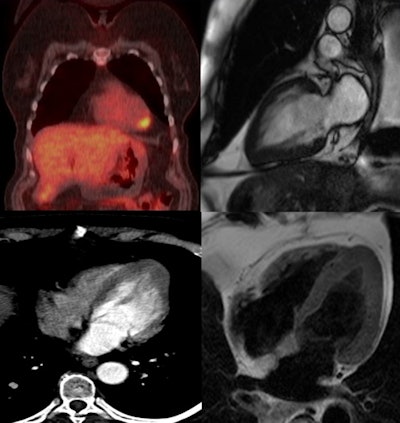

Whole-body PET/CT (top left) shows lung cancer and FDG avidity at the left ventricular apex. Image courtesy of Dr. Esin Gezmis.Also resulting in cardiac FDG activity are inflammatory lesions like myocarditis, which tends to show regional uptake, and endocarditis, in which avidity at the valves is seen. Focal FDG uptake can also be observed due to cardiac involvement of sarcoidosis, particularly in the acute inflammatory stage, but it is difficult to differentiate it from cardiac neoplasms and metastasis, according to Gezmis.

At the Milan meeting, Gezmis reported about the case of a lung cancer patient with focal cardiac FDG uptake on whole-body oncological PET/CT, which turned out to reflect apical HCM when further evaluated with CMR.

A subsequent whole-body FDG-PET/CT scan showed uptake in the mass and right hilar lymph node, confirming the diagnosis, but increased focal activity was also noted at the apex of the left ventricle, which appeared to be within the wall rather than the lumen. This raised the possibility of cardiac metastasis, which would have changed the management of the patient, and further evaluation was required.

Despite the fact it was not ECG-gated, the thoracic CT scan was reassessed regarding the heart by putting the images into true cardiac planes using multiplanar reconstruction. This demonstrated the loss of tapering of myocardium from the base to the apex with thickening of distal walls, suggesting apical HCM.

Contrast-enhanced cardiac MRI was performed to rule out metastasis and validate the apical HCM diagnosis. The images showed disproportionate and focal wall thickening in the left ventricular apex, which corresponded with the area of avidity on the PET/CT scan. There was also a "spade-like" configuration of the apical left ventricular cavity, and contractility of myocardium was preserved.